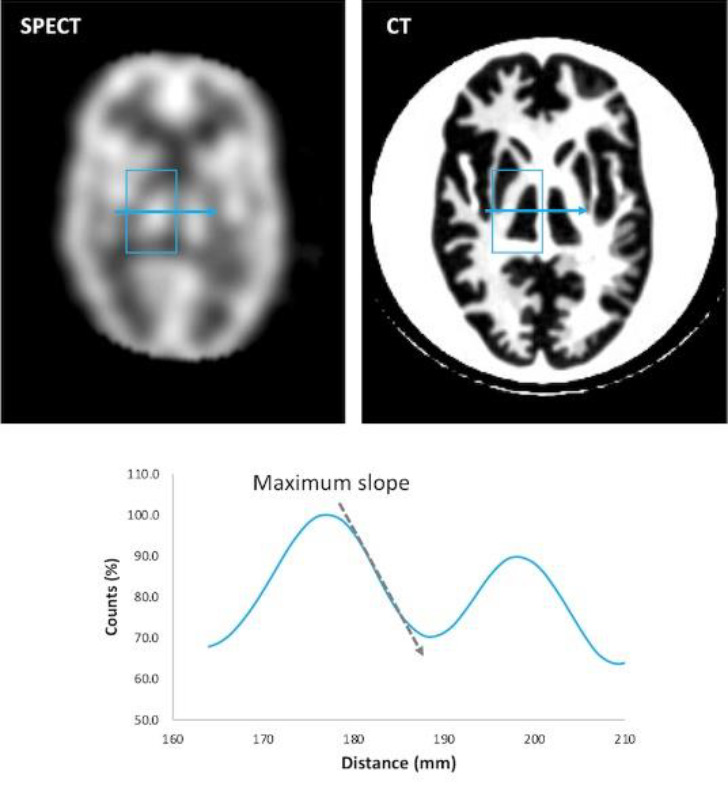

Methods: SPECT images of the brain phantom were acquired from eight devices in five institutions. The phantom was filled with 28 kBq/ml of 99mTc solution at the start of scanning. We obtained various data with different acquisition times under clinical reconstruction and acquisition conditions at each institution. Four physical parameters (percent contrast, contrast noise ratio (CNR), asymmetry index (AI), and sharpness index (SI)) were measured with the phantom. Seven observers blindly evaluated all image series and scored them on a scale of 1-3 using four checkpoints: contrast, image noise, symmetry, and sharpness. The average score for all observers was calculated.